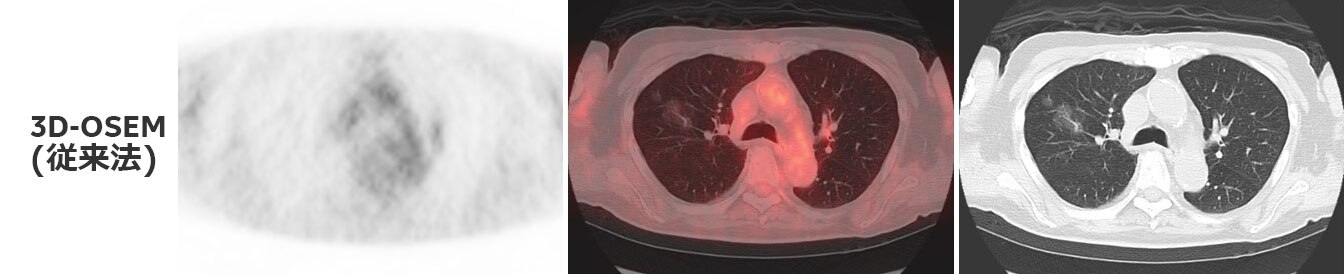

CT上にて肺野にすりガラス像を認め、PET画像上で淡いながらも集積を認められます(Fig.2)。

3D-OSEM(従来法)で再構成した画像では、すりガラス像に一致した部位の集積は明らかではありません。Q.Clearを用いて再構成した画像では、淡いながらもすりガラス像に一致した集積が認められます。また、Q.Clearを用いて再構成した画像では、従来法と比べてノイズが低減されています。

すりガラス像部でのSUV測定結果は、従来法でSUVmax 0.69、SUVmean 0.48、Q.ClearでSUVmax 0.81、SUVmean 0.59となっており、Q.Clearで集積は増加しています。

また、すりガラス像の周辺肺野では従来法でSUVmax 0.58、SUVmean 0.43、Q.ClearでSUVmax 0.46、SUVmean 0.39となっており、Q.Clearで集積は低下し、そのピクセル毎のばらつきも抑えられています。

従来法では病変部とその周囲においてSUV値の変化量が少なく、集積無しとなっていたものが、Q.Clearでは淡いながらもコントラストが得られて集積として認めるようになりました。